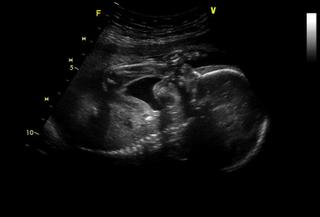

Ahoj, tak zase jsem na vysledek testu cekala az do druheho dne 😉 Ale dobry, jsem 19. den po ET bez PK a mam hCG 4165IU/ml, takze porad jsou ve hre dvojcata 😉 Na US jdu za 12 dni, to uz bude slysitelne i srdicko(ka), ktere by melo zacit bit dneska, jdu k Langerove, u ktere jsem zacinala a ktera me naposled videla, kdyz mi podruhe oddalovala stimulaci kvuli cyste 😉

@tereza1980 - tiež krásna foto 🙂 máte aj nožičky, narozdiel od nás 😉